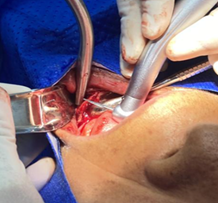

Luego se realiza un acceso quirúrgico con un bisturí y una hoja #15, haciendo una incisión en la encía muy cerca del área del reborde donde se va a remodelar, la ubicación y la longitud va a depender de la extensión de las irregularidades que tuvo el paciente, en este caso fue una incisión a lo largo de toda la parte anterior en el área de canino a canino, luego se separa la encía suavemente con el periostótomo para lograr la exposición del hueso subyacente, para llegar a la parte primordial que es la remodelación ósea (Figura 4).

Figura 4. Procedimiento quirúrgico.

Elaboración: Los autores.

Con la ayuda de la turbina y fresas, específicamente una freza zecrya o una maxicut se empieza el fresado del hueso para su reducción, al mismo tiempo con ayuda de los dedos se palpa el nivel óseo para verificar que este sea similar, con una lima de hueso se raspa el borde alveolar para mejorar su exactitud eliminando excesos óseos, nivelando irregularidades y sobre todo dando la forma al hueso para prepararlo para la futura prótesis, este proceso es considerado una osteotomía mandibular, que consiste en la eliminación o remodelación selectiva de una parte del hueso, en este caso mandibular, para la corrección de problemas estéticos o estructurales, la técnica puede variar dependiendo del objetivo clínico del odontólogo, puede ser para eliminación de hueso restante, preparación para implantes, prótesis dentales, o corrección de deformidades óseas (Figura 5).

Figura 5. Proceso de osteotomía mandibular.